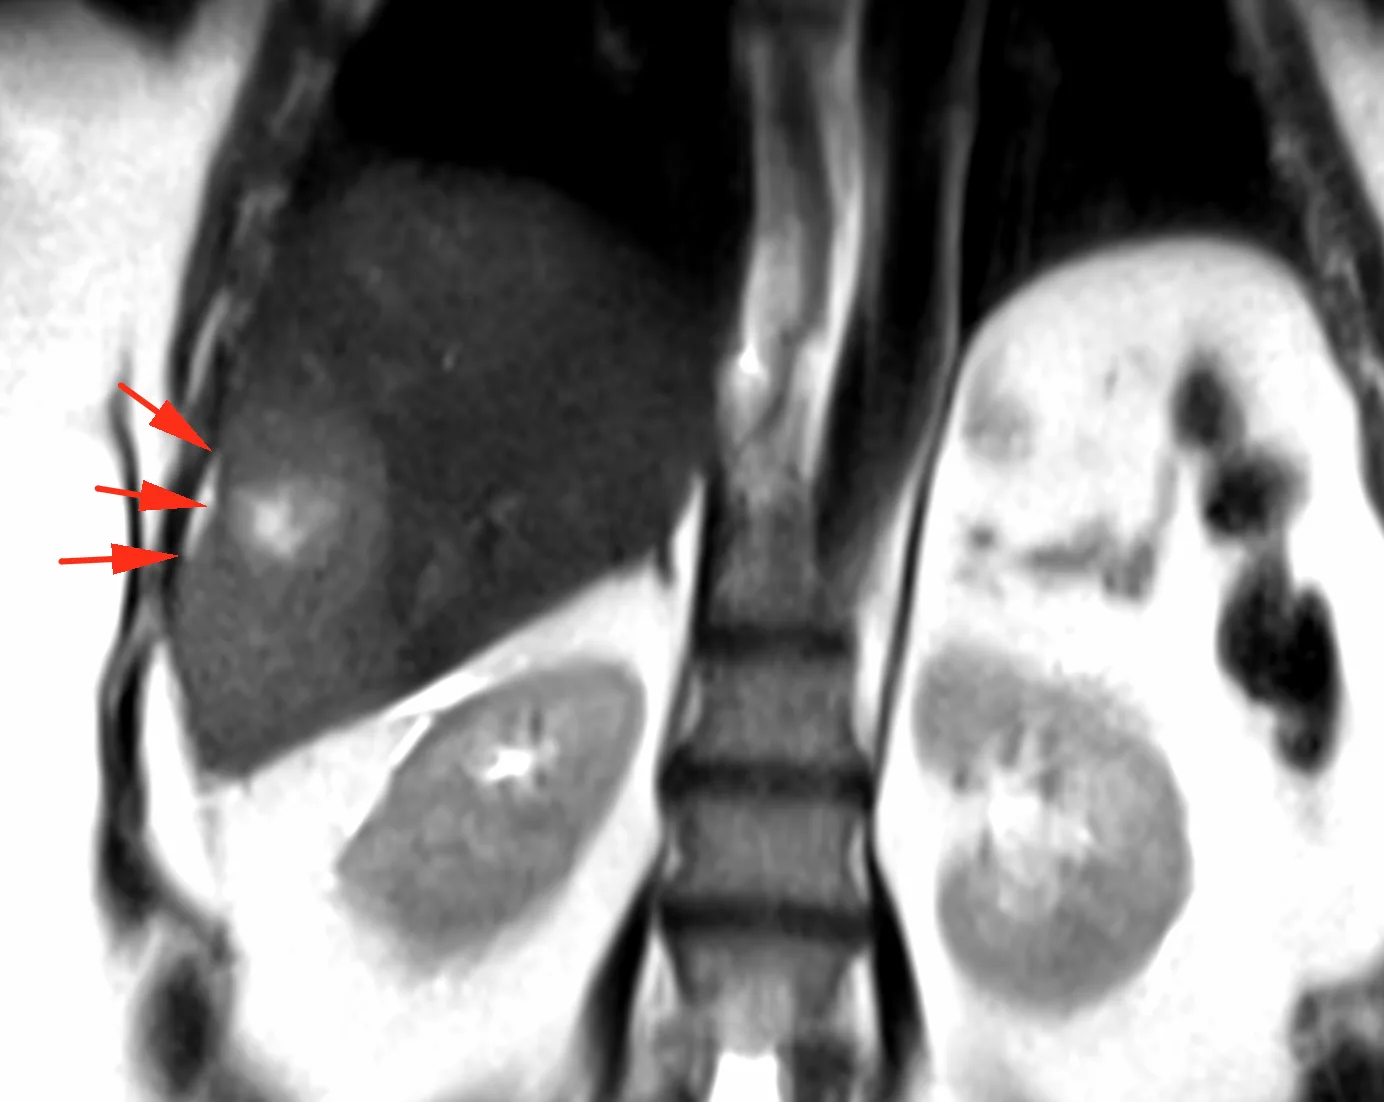

ЖЕНЩИНА 38 лет, фокальное изменение печени выявлено на УЗИ.

Повторные #КТ (с разницей в 2,5 месяца) без динамики. Имеется медленное, постепенное, слабоинтенсивное накопление контраста от периферии к центру.

На #МРТ - очень высокий сигнал на Т2, низкий на Т1, «лучистые» контуры. Истинное ограничение диффузии (ADC=460±109х10-6 кв.мм/с). Накопление контраста такое же, но на МРТ лучше видны краевое узелков накопление в артериальную фазу, тотального контрастирования нет даже на отсроченной фазе (через 5 минут).

Картина характерна: это гиалинизированная/ #склерозированнаягемангиома. Характерное стяжение контура является свидетельством склерозирования: уменьшения объёма, «рубцевания».

Гемангиомы с суженными кавернозными пространствами из-за склероза имеют большее количество более толстых и неровных перегородок, которые могут препятствовать диффузии молекул, что приводит к снижению значений ADC.

Склерозированные гемангиомы печени — это редкие доброкачественные поражения, которые часто трудно отличить от злокачественных, ибо они не имеют типичных для кавернозных гемангиом признаков.

Но! Часть признаков все равно сохраняются:

1. Значительный гиперсигнал на т2

2. Резкие, хоть и неровные, контуры

3. Центрипетальное, и иногда с приставочными узелками накопления контраста на артериальной фазе, контрастирование, пусть и неполное.

4. Стабильность в динамике